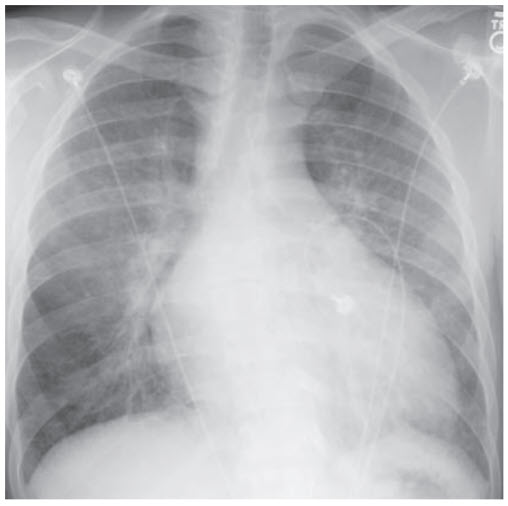

A 59-year-old man presents with complaints of cough and difficulty breathing. Over the last few days, his dyspnea has progressed to the point where he is short of breath unless resting in a seated position. His cough is nonproductive. He has a history of coronary artery disease and alcoholism. On examination, the patient appears uncomfortable; he is afebrile with a blood pressure of 123/72 mmHg, heart rate of 92 beats per minute, and respiratory rate of 24 breaths per minute. He is obese with a BMI of 36 kg/m2 . His heart sounds are distant and he has pitting edema of his lower extremities. A bedside ultrasound is of poor quality given the patient’s body habitus; however, the inferior vena cava (IVC) is enlarged and the width does not change during the respiratory cycle. A serum ethanol level is negative. His other laboratory tests and chest x-ray (Figure below) are shown below:

Congestive heart failure. The given history is fairly straightforward for CHF, with a description of dyspnea, orthopnea, and a history of coronary artery disease and alcoholism (both of which can contribute to heart failure). A normal ultrasound shows some collapse during inspiration, which is a normal response to decreased intrathoracic pressure. This patient’s IVC is enlarged and fixed during the respiratory cycle, suggesting volume overload; this is helpful since the jugular venous pulsations may be difficult to appreciate in an obese patient. The chest x-ray shows bilateral pulmonary edema that results from increased hydrostatic pressure in the pulmonary circulation. The one trick to this question is the false-negative brain natriuretic peptide (BNP). BNP is a peptide released primarily by the ventricles in response to increased filling pressures seen in the setting of heart failure. Normally, BNP is extremely sensitive and therefore a negative result pretty much rules out this diagnosis; however, false negatives are reported in obese patients and therefore this diagnosis should still be considered.